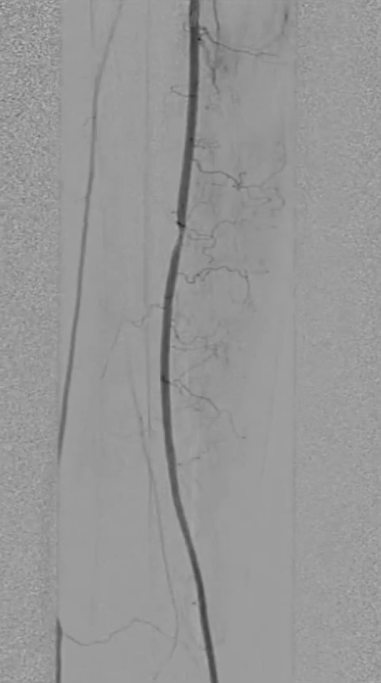

穿刺右侧股总动脉,置入8F翻山鞘,行左下肢动脉造影,可见左股浅动脉长段闭塞,远端流出道尚通畅。

既往支架已遮盖股浅动脉起始段